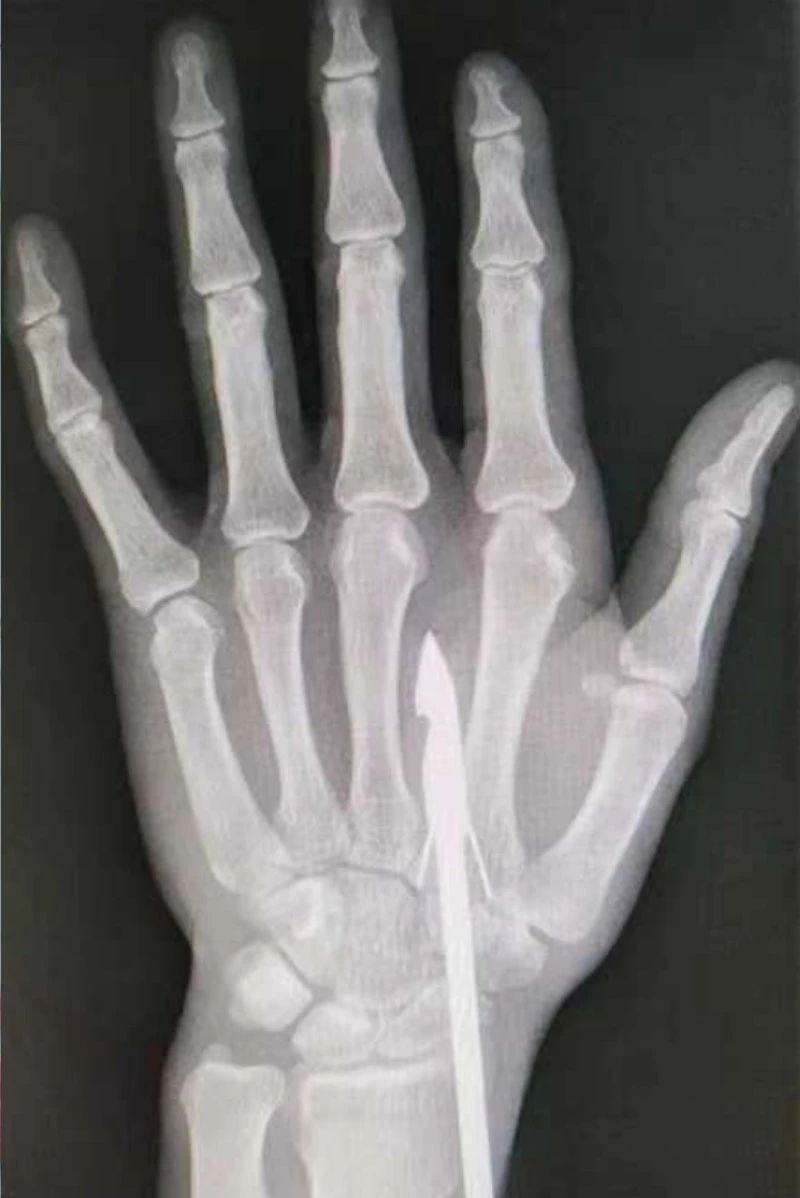

時(shí)間緊迫,每一秒的流逝都可能對(duì)傷者的手部功能造成不可逆的損害。接診醫(yī)生代彭威,迅速對(duì)傷者進(jìn)行了初步檢查。他注意到,魚鉤已經(jīng)深深嵌入皮膚,情況遠(yuǎn)比表面看起來復(fù)雜。沒有絲毫猶豫,立即安排了X線檢查以確認(rèn)魚鉤的位置及傷及范圍,以及急診化驗(yàn)檢查以評(píng)估患者的整體狀況。

確保在取出魚鉤的同時(shí),不對(duì)周圍的組織造成額外的傷害。8點(diǎn)15分左右患者在局部浸潤麻下進(jìn)行手術(shù),經(jīng)探查后魚鉤未傷及重要血管、神經(jīng)及肌腱,經(jīng)過緊張的十分鐘,魚鉤終于被順利取出,隨后對(duì)傷口進(jìn)行了仔細(xì)的清理和縫合,用敷料仔細(xì)包扎,確保傷口能夠順利愈合。